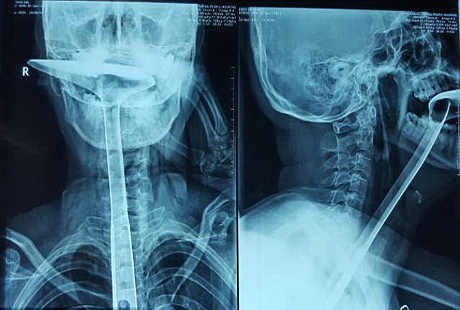

Karena Guan sedang berada di dapur, ia pun mengambil spatula dengan gagang sepanjang 30 cm, dan mencoba memasukkannya ke tenggorokan. Tapi cara ini nyatanya tak manjur, karena Guan justru panik ketika mendapati alat masak itu tersangkut di tenggorokannya, dan tak bisa dikeluarkan.

Putrinya yang masih berusia empat tahun lantas membawa ibunya keluar dari apartemen dan meminta petugas keamanan untuk memanggilkan ambulans. Sang ibu dilarikan ke Kanghua Hospital, Dongguan, di Provinsi Guangdong. Setibanya di sana, dokter melihat si pasien menelan seluruh gagang spatula tersebut, dan hanya menyisakan bagian kepala spatulanya saja.

Tindakan operasi darurat pun digelar. Setelah beberapa jam, spatula itu akhirnya berhasil dikeluarkan. Sayangnya tim dokter juga harus memotong esofagus atau kerongkongan wanita berusia 31 tahun itu karena kerusakan yang diakibatkan oleh si spatula. Guan pun kehilangan kerongkongannya sepanjang 20 cm.